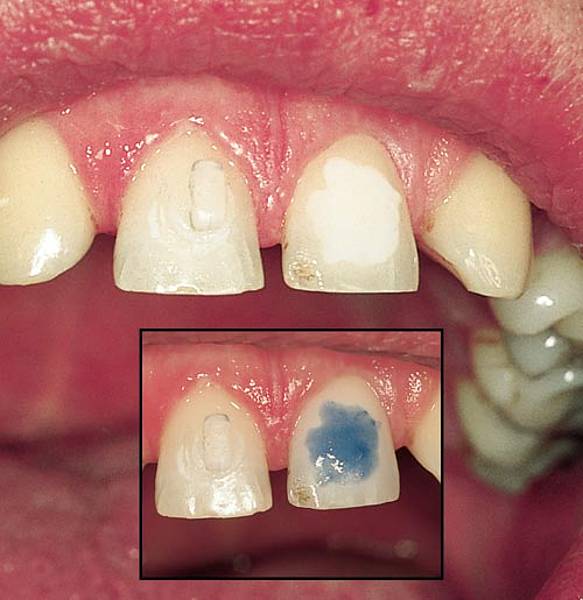

Vococid Vococid wird für die SäureÄtzTechnik verwendet und enthält 35% Orthophosphorsäure Die blaue Einfärbung des Gels bzw der Flüssigkeit ermöglicht eine sichere Applikationskontrolle Vococid kann zur Schmelzätz oder TotalEtchTechnik verwendet werden und ist wahlweise als Gel oder Flüssigkeit erhältlich Produktdetails Vococid. ÄtzTechnik Diese Technik ist eine kalte Veredelungstechnik und wird mittels Säure, welche direkt auf das Glas aufgebracht wird, durchgeführt Die Glashütten haben verschiedene Rezepte, bei denen Chemikalien mit Flusssäure oder mit Schwefelsäure angerührt und auf das Glas gebracht werden Das Glas wird dadurch matt. Schmelzveränderungen infolge SäureÄtzTechnik und Debonding von Brackets (lokal intraoral, moderat, irreversibel) Bei der Befestigung von Brackets mittels SäureÄtzTechnik sind geringe Oberflächenveränderungen fast unvermeidbar (inhärente Komplikation) Bei klassischen BondingSystemen sind 10 bis µm Zotten zu erwarten, die in den.

Vococid Vococid wird für die SäureÄtzTechnik verwendet und enthält 35% Orthophosphorsäure Die blaue Einfärbung des Gels bzw der Flüssigkeit ermöglicht eine sichere Applikationskontrolle Vococid kann zur Schmelzätz oder TotalEtchTechnik verwendet werden und ist wahlweise als Gel oder Flüssigkeit erhältlich Produktdetails Vococid. In einem zweiten Schritt wird bei dem als SäureÄtzTechnik bezeichneten Verfahren die aufgeraute Oberfläche des Zahns mit einem Monomerengemisch versetzt Die Monomeren gelangen in die Hohlräume und polymerisieren dort aus Dadurch kommt es zur engen Verbindung von Zahnschmelz und Polymerisat. SäureÄtzTechnik Die SäureÄtzTechnik ist eine Füllungstechnik, bei der vor dem Einbringen des plastischen Füllungsmaterials in die Kavität die Zahnhartsubstanz mit Hilfe von Säuren angeätzt wird.